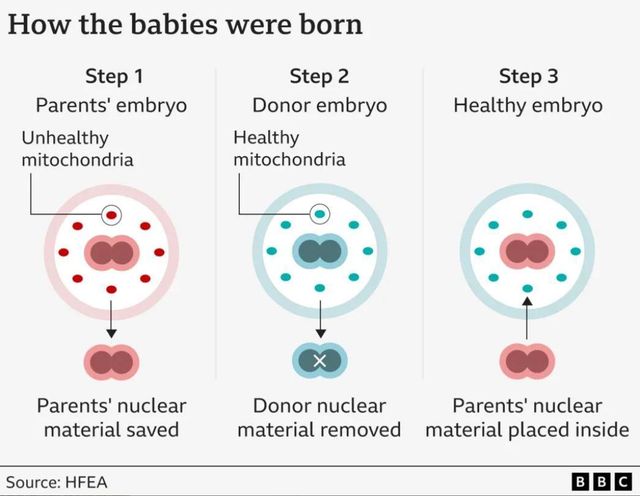

이 방법은 엄마의 난자와 아빠의 정자에 여성 기증자의 두 번째 난자를 결합하는 방식으로, 치명적인 미토콘드리아 질환을 방지한다.

미토콘드리아는 엄마를 통해서만 유전된다. 따라서 이 선구적인 기술은 부모와 건강한 미토콘드리아를 기증하는 여성 모두를 필요로 한다.

엄마와 기증자의 난자는 아빠의 정자와 함께 실험실에서 수정된다.

배아는 정자와 난자의 DNA가 전핵(pro-nuclei)이라는 한 쌍의 구조를 형성할 때까지 발달하는데, 여기에는 머리카락 색과 키와 같은 인체 구축을 위한 청사진이 포함되어 있다.

양쪽 배아에서 전핵을 제거하고 부모의 DNA를 건강한 미토콘드리아를 가진 배아 안에 삽입한다.

이렇게 태어난 아이는 유전적으로 부모와 관련이 있지만, 미토콘드리아 질환은 가지고 있지 않을 것으로 기대된다.